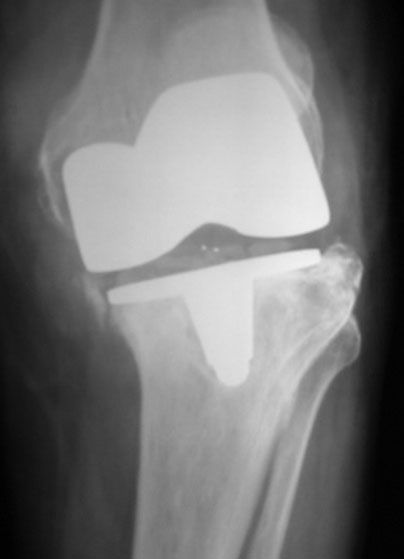

Failed TKR

Revised TKR